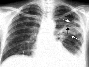

GUATR HASTALIĞI NASIL TEŞHİS EDİLiR?

Boyun muayenesi,Boyun muayenesi sırasında tiroid bezinin büyüklüğü,sertliği ve içinde nodül olup olmadığı saptanabilir.Boyun bölgesine dışarıdan bakıldığında ,normalde tiroid bezi görülemez.

Fakat tiroid bezi büyümüş olan hastalarda özellikle yutkunmakla hareket eden bir şişlik farkedilir.

Tiroid ultrasonografisi(Tiroid bezinin iç yapısı görülür)

Tiroid sintigrafisi(Tiroid bezinin fonksiyonel durumu görülür)